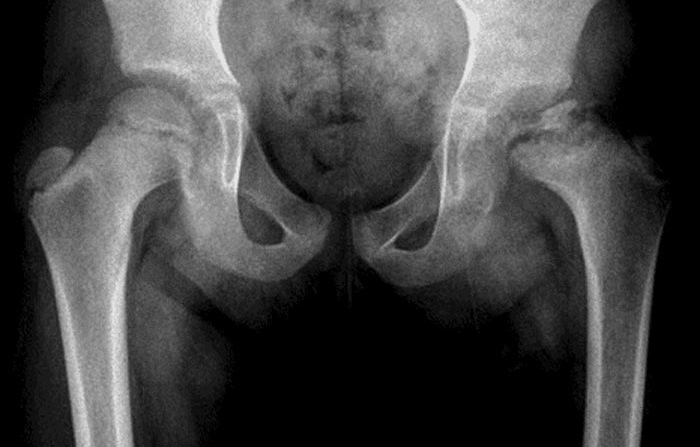

A 7-year-old boy is brought to the office for evaluation of chronic left thigh pain and a limp.  The pain began 8 months ago as an intermittent ache, especially after soccer practice.  The patient's family thought his symptoms were growing pains and have been giving him ibuprofen as needed for pain, with some improvement.  Over the past month, however, the pain has been constant, and the patient recently developed a limp.  He has had no fever, additional joint pain, or chronic medical problems and takes no daily medications.  While walking to the examination table, the patient avoids bearing full weight on the left leg.  Examination shows significantly limited range of motion of the left hip and atrophy of the left proximal thigh muscle.  The remainder of the examination is unremarkable.  X-ray of the pelvis is shown in the image. A 7-year-old boy is brought to the office for evaluation of chronic left thigh pain and a limp.  The pain began 8 months ago as an intermittent ache, especially after soccer practice.  The patient's family thought his symptoms were growing pains and have been giving him ibuprofen as needed for pain, with some improvement.  Over the past month, however, the pain has been constant, and the patient recently developed a limp.  He has had no fever, additional joint pain, or chronic medical problems and takes no daily medications.  While walking to the examination table, the patient avoids bearing full weight on the left leg.  Examination shows significantly limited range of motion of the left hip and atrophy of the left proximal thigh muscle.  The remainder of the examination is unremarkable.  X-ray of the pelvis is shown in the image.   Which of the following is most likely responsible for this patient's condition? A) Bone infection B) Malignancy C) Muscular dystrophy D) Osteonecrosis E) Slipped epiphysis F) Stress fracture G) Synovitis Which of the following is most likely responsible for this patient's condition?